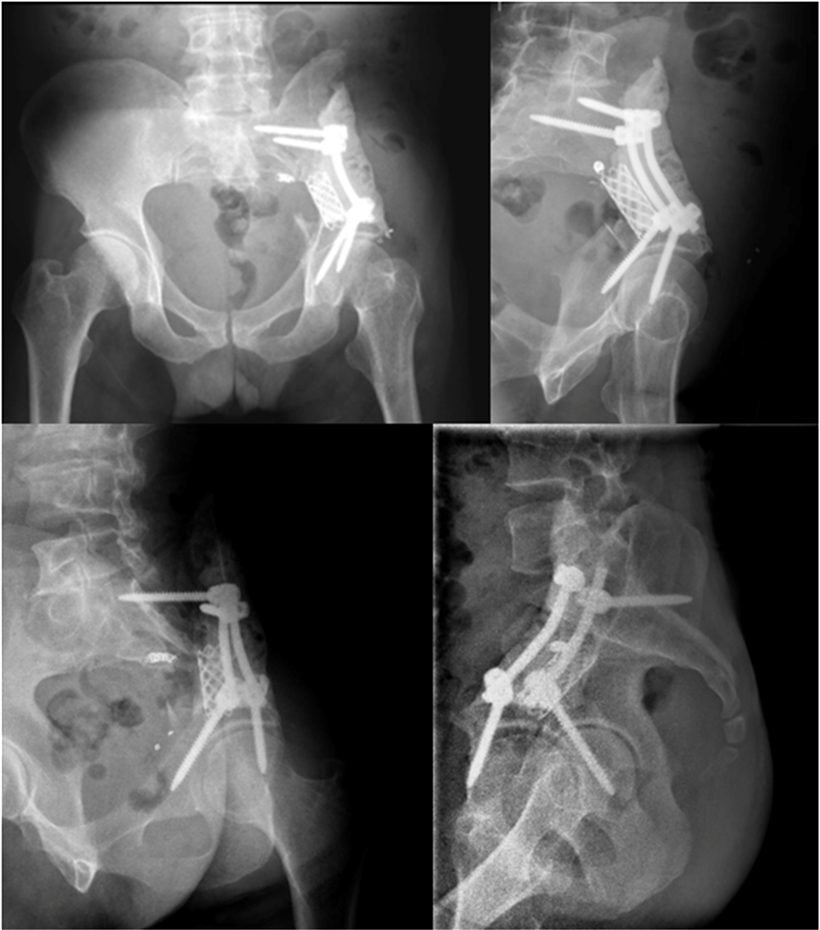

充分考虑患者后续治疗需求及减轻经济负担,手术团队巧妙设计了利用椎弓根螺钉联合钛棒及钛网重建骨盆稳定性的手术方案。针对肾癌骨转移瘤血供丰富、术中易大量出血的特点,术前团队根据血液科意见为患者输注血浆纠正凝血异常,并由血管外科医师在术前一天实施肿瘤血管栓塞术,以最大限度控制术中出血。

术中,手术团队在完整剥离巨大肿瘤的同时,精细保护并松解受压的血管与神经组织。肿瘤完整切除后,针对髋臼顶部骨缺损区,团队于髋臼前后侧、骶骨及残留髂骨处精准植入椎弓根螺钉,截取合适长度钛网进行填充,并以钛棒连接螺钉加压固定,最后利用骨水泥重塑髂骨外形,构建成坚固的“钢筋水泥”结构。整台手术历时约4小时,过程顺利,出血量仅600毫升。

术后影像显示,螺钉及钛棒位置良好,固定牢固。